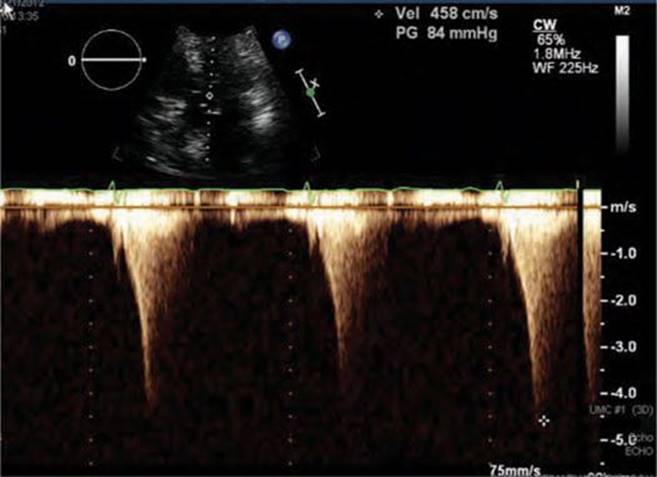

Physical examination revealed a systolic murmur that worsens with rapidly standing, squatting, and standing again. A 12-lead ECG reveals prominent QRS voltage in the precordial leads with deep T-wave inversions (Figure 53-1). An echocardiogram was obtained demonstrating a nearly 5 cm ventricular septum and mitral regurgitation secondary to systolic anterior motion of the mitral valve (SAM) (Figures 53-2 to 53-5). A resting left ventricular outflow tract (LVOT) gradient of 45 mm Hg was recorded with a provocable gradient of >80 mm Hg (Figure 53-6).

FIGURE 53-6 LVOT gradient after provocation with peak gradient recorded as 84 mm Hg.

Screening with transthoracic echocardiogram should be performed at the time of the initial evaluation and yearly thereafter in known HCM patients and is recommended at the time of initial screening of first-degree relatives to assess left ventricular systolic and diastolic function, wall thickness, and outflow tract gradients.1-3,5 The obstruction that occurs in HCM has been shown to be due to mitral valve systolic anterior motion (SAM) with mitral-septal contact (best illustrated in Figures 53-5 and 53-7B), muscular obstruction in the midcavitary region, or anomalous papillary muscle insertion into the anterior mitral leaflet.1,2,6 The peak LVOT or midcavitary gradient should be measured at rest, and if <50 mm Hg, the test should be repeated with provocative measures such as exercise, Valsalva maneuver, or potentially amyl nitrate, with the latter rarely required in the current era. Provocation with dobutamine infusion during echo is no longer recommended. Upon testing, one-third of patients will have a resting LVOT gradient >30 mm Hg (obstructive HCM), one-third will have resting gradients <30 mm Hg (nonobstructive HCM), and a final one-third will have normal resting gradients but provoked gradients >30 mm Hg (labile obstruction).1,2,6